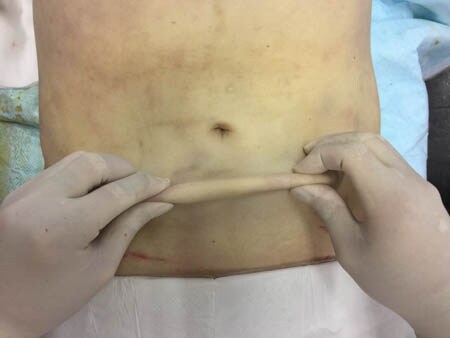

上の画像の部分をつまんでみましょう。

↓ ↓ ↓